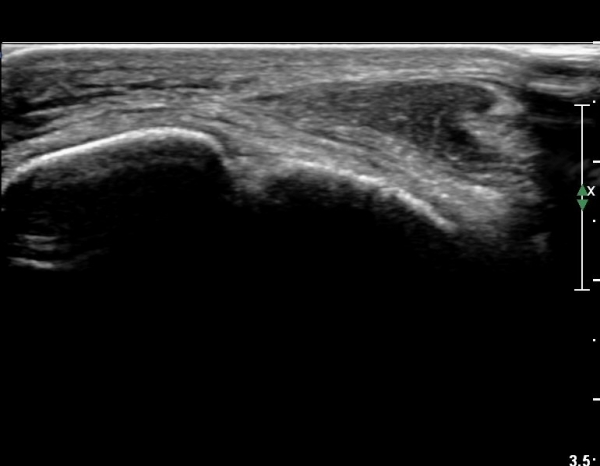

¹ß¸ñ À§¿¡¼­ ¸»´Ü ¾ÕÂÊ °æ°ñºñ°ñÀδë Á¾´Ü¸é°Ë»ç¿¡¼­ ƯÀÌ ¼Ò°ßÀ» º¸ÀÌÁö ¾Ê´Â´Ù(»çÁø 2, 3).